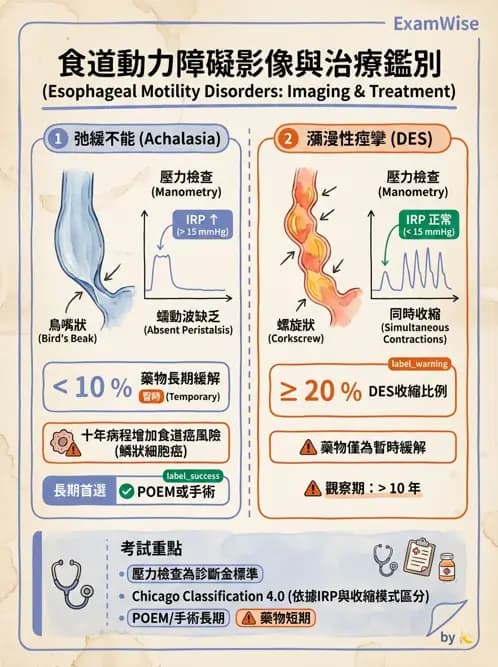

本題主軸在於食道動力障礙的鑑別:圖A呈現食道近端擴張伴下括約肌呈尖狀(bird’s-beak)狹窄,是典型的achalasia;圖B呈現多處非協調性收縮,形似rosary-beads或corkscrew,是diffuse esophageal spasm(DES)。

選項分析

- 選項A

Achalasia及DES皆可表現為吞嚥異常,DES尤其以胸痛(noncardiac chest pain)為主訴,achalasia則以漸進性吞嚥困難為首,但也可有胸悶、胸痛。兩者臨床上確實均可出現胸痛及吞嚥異常。 ([pubs.rsna.org](https://pubs.rsna.org/doi/